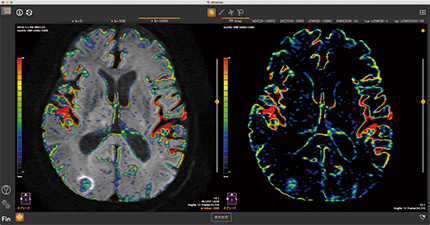

PP-map

b値の異なる3つのDWIからIVIMにおける灌流割合を計算するため、従来のものより撮影時間が大幅に短縮されます。ADCも同時に計測し、組織をパラメトリックに解析可能です。